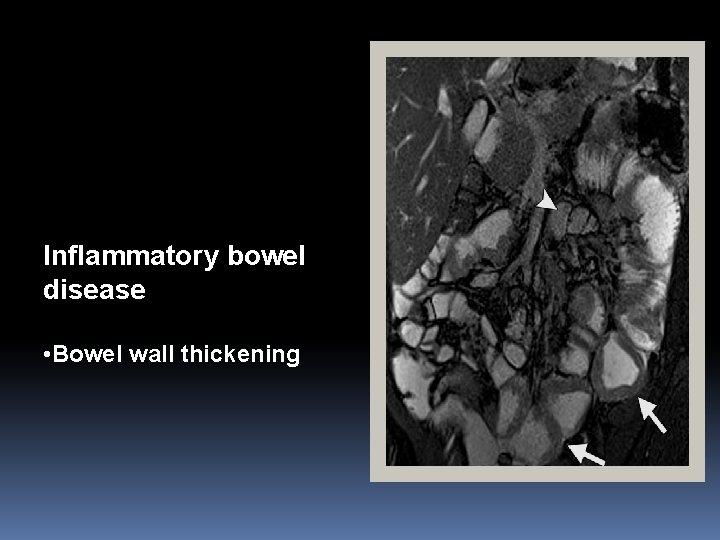

Inflammatory bowel disease • Bowel wall thickening